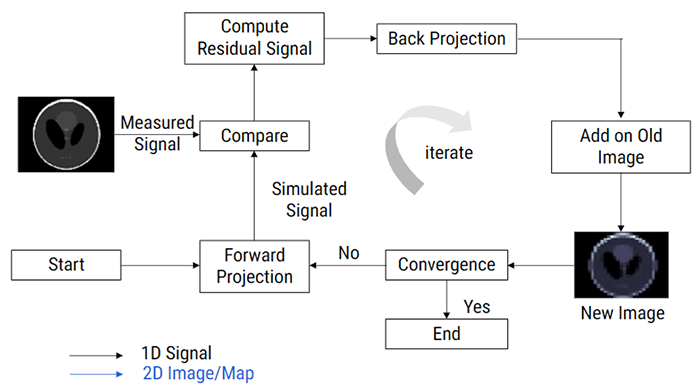

Dose Modulation Techniques

Radiation exposure to the patient has become a concern for the radiologist in the multidetector computed tomography (CT) era. With the introduction of faster multidetector CT scanners, various techniques have been developed to reduce the radiation dose to the patient; one method is automatic exposure control (AEC).

Let’s look at the various dose modulation techniques that are available that help reduces patient dose. CARE Dose 4D (Siemens) assesses the size of the patient cross-section being scanned and adjusts tube current relative to the reference effective milliamperage. It aims to provide adequate image noise, which varies depending on the size of the patient. This system operates on the principle that different-sized patients require different levels of noise to maintain adequate image quality.

SMART mA

Another dose modulation technique is known as SmartmA (GE) which allows the user to set diagnostic image quality by entering the “Noise Index” and a range of acceptable tube current settings (minimum and maximum milliamperage). The AEC system from one vendor, GE, has two elements: AutomA and SmartmA. AutomA provides the patient-size and z-axis AEC elements, and SmartmA provides the rotational AEC element.

SUREExposure

SUREExposure adjusts the tube current appropriately for the selected acquisition and reconstruction parameters and dose reduction algorithms. SUREExposure tube current modulation can reduce patient dose while maintaining image quality.